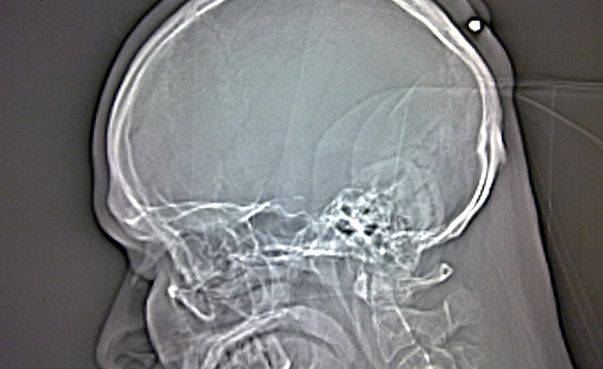

A trăit 23 de ani cu un glonţ în cap

Medicii i-au făcut o radiografie şi astfel au văzut glonţul, pe care l-au îndepărtat cu succes pe cale chirurgicală.